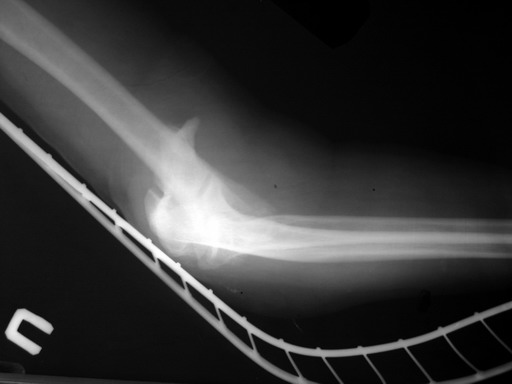

Солидарен с мнением обоих Александров (Челнокова и Рыкова): точную репозицию такого перелома вряд ли удастся выполнить закрыто. Даже во время открытого вмешательства это сделать непросто. Неслучайно предложен костно-пластический доступ с временным отсечением локтевого отростка. И по методу фиксации согласен с Александром Челноковым: 2 пластины. В качестве примера привожу рентгенограммы одного из наших пациентов с аналогичным повреждением.